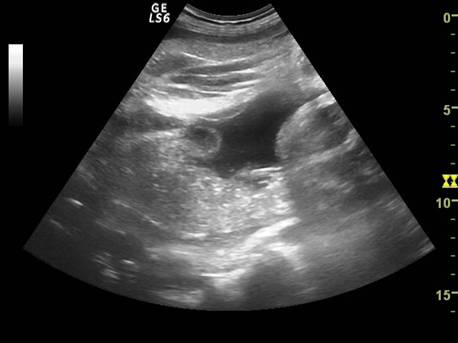

Fig. nr. 239 Aparitia de bule in cavitatile toracica si abdominala ( sageti ), dupa maceratie la fatul mort intrauterin , la 34 sapt.